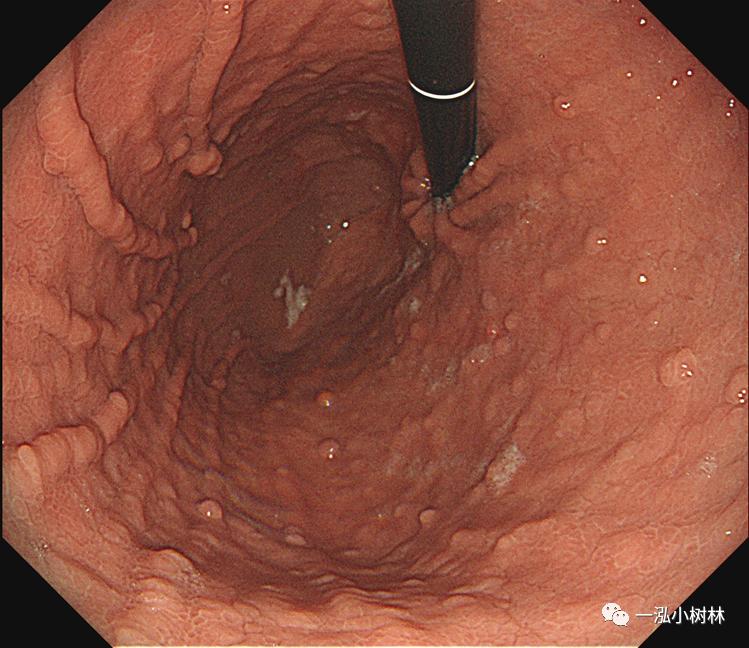

F 23,上腹部不适1年。

白光内镜:胃体多发息肉

白光内镜:胃体、底、贲门多发息肉